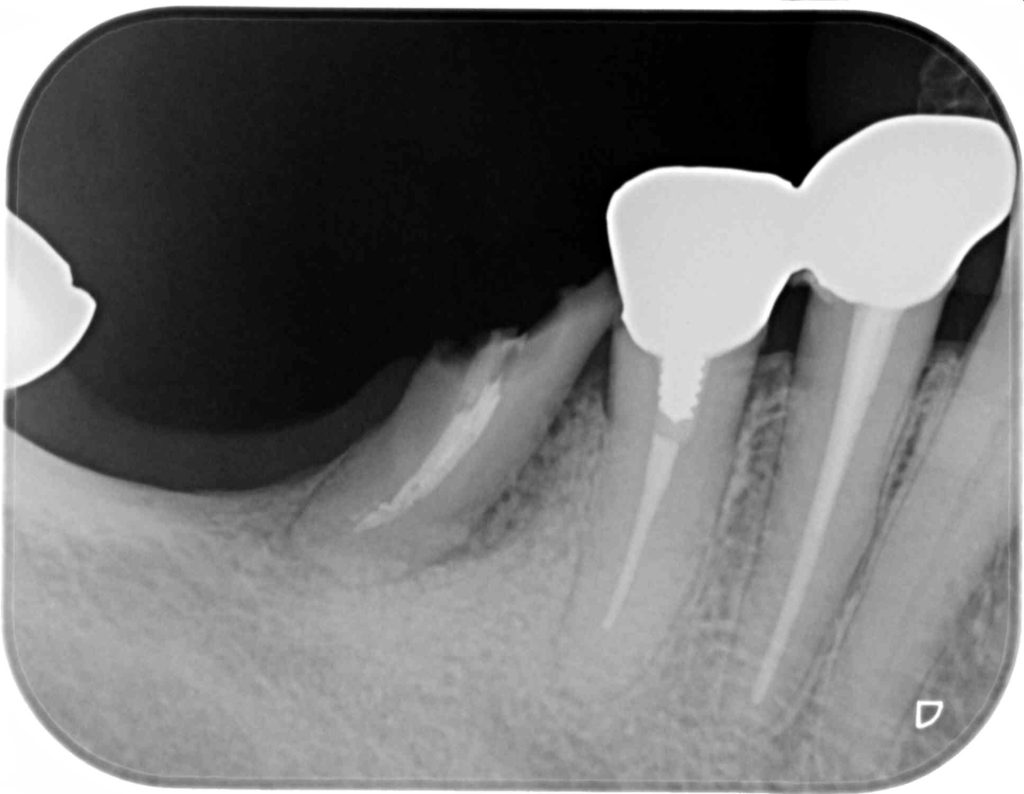

下記の症例はインプラントだけ埋入すれば良いわけではありません。

周囲環境を整え長期的に安定し、長持ちさせるインプラントを目指す必要があります。

その為に歯肉を移植しインプラント周囲に強い抵抗力を持つ歯肉を作る事が大切です。